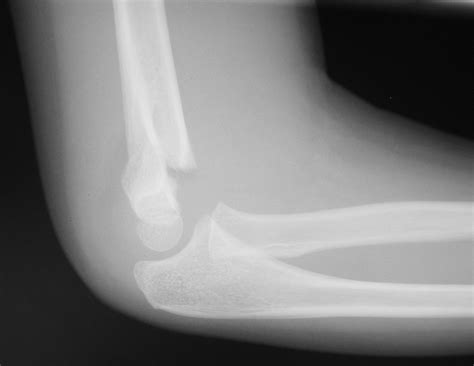

Fracture blisters occur around the region of a broken bone, specifically in areas where there is very less fat between the bone and the skin, such as: Fracture blisters occur on skin overlying a fractured bone, and fractures complicated by the development of overlying blisters remain a clinical dilemma in orthopedics.:43.

Etiology represents a combination of excessive swelling and. Fracture blisters are a rare occurrence after you fracture or break a bone. Fracture blisters occur on skin overlying a fractured bone, and fractures complicated by the development of overlying blisters remain a clinical dilemma in orthopedics.:43.

Fracture blisters occur on skin overlying a bone fracture, and fractures complicated by the development of overlying blisters remain a clinical dilemma in orthopedics. Fracture blisters can be seen in open fractures, but are rare. Va doctors postponed surgery to give the blisters time to heal. Large fracture blisters swelled over his injury while he traveled from his cabin to the clinic and on to seattle. Fracture blisters can occasionally be seen to form even after uneventful elective foot and ankle surgery (figure 2). I underwent a wide resection surgery to remove a desmoid tumor. Etiology represents a combination of excessive swelling and. Fracture blister on wn network delivers the latest videos and editable pages for news & events, including entertainment, music, sports, science and more, sign up and share your playlists. Desai a clinical and histological study was performed on fracture blisters found in association with 13. Often showing up days after an injury, it can make people nervous that something is going wrong. I have several fracture blisters along my incision. A prospective study of 53 cases. Varela cd, vaughan tk, carr jb, slemmons bk. A fracture blister will usually appear about two and a half days after an injury. Questions and answers on fracture blisters. Fracture blisters occur on skin overlying a bone fracture, and fractures complicated by the development of overlying blisters remain a clinical dilemma in orthopedics. Technical called a hemorrhagic blister, which in my case represent a more severe injury where the dermis is completely stripped of epidermal cells.